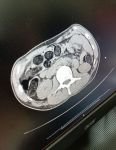

İl Emniyet Müdürlüğü Narkotik Suçlarla Mücadele Şube Müdürlüğü ekipleri tarafından Doğu illerinden İstanbul’a giden bir yolcu otobüsü polis ekipleri tarafından şüphe üzerine kontrol noktasında durduruldu. Yolcu otobüsünde bulunan bir kişinin şüpheli davranışlar sergilemesi dikkat çekti. 41 yaşındaki işçi Şefik B'nin uyuşturucu maddeyi kapsüller halinde yutarak taşıdığı tespit edildi. Şüphelinin çekilen röntgeninde midesinde çok sayıda kapsül olduğu belirlendi. Şüphelinin midesinden 48 parça kapsül halinde 542 gram eroin çıkarıldı.